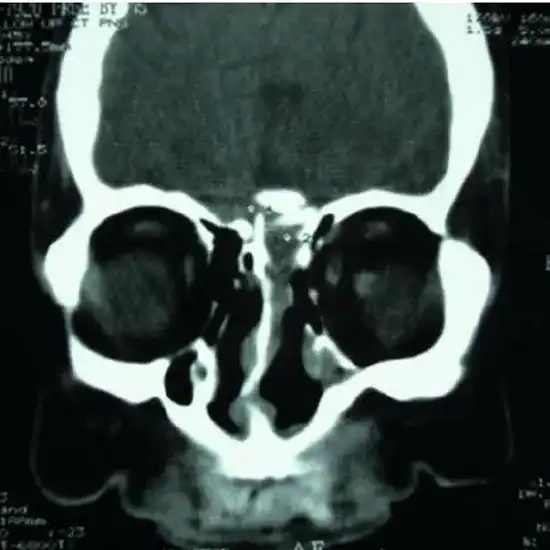

Contrast-enhanced computed tomography (CECT)-Cheek  is an imaging procedure used to visualize puffy cheek and soft tissue structures present nearby cheeks. It provides a clear detailed image so as to help a doctor to detect the concerned problem.

CECT Cheek scan is an imaging technique that is used as a diagnostic procedure. It is usually used for puffy cheeks and soft tissue of the cheeks region. The scan produces a clear, detailed, and high-resolution image of the region that help your doctor to diagnose, detect, and plan the treatment for the problem.

The CECT cheek scan shows the eyes, sinuses (air-filled cavities) around the nose, facial bones, the inner ear, and the nose.